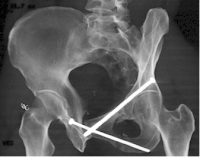

Another plain pelvic film identified left sided peripheral superior and mid-inferior pubic ramus fractures.

Pelvic computed tomography confirmed the diagnosis and detailed the well-aligned hypertrophic nonunion sites. There were no other areas of fracture or instability seen on these imaging studies.

At surgery, medullary screws were inserted through small stab wounds under fluoroscopic guidance to stabilize the nonunion sites. First the superior ramus site was fixed with an antegrade superior ramus medullary lag screw. The inferior ramus site was then secured using a large cortical lag screw.